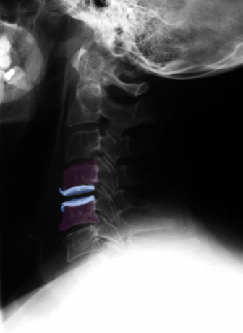

Πρόσθια αυχενική δισκεκτομή και τοποθέτηση τεχνητού αυχενικού δίσκου (μπλέ) Α6-Α7. |

Πρόσθια αυχενική δισκεκτομή και τοποθέτηση τεχνητού αυχενικού δίσκου (μπλέ) Α6-Α7. Ακτινογραφίες με τον αυχένα σε ουδέτερη θέση (αριστερά), έκταση (κέντρο) και κάμψη (δεξιά). Αναδεικνύεται η κίνηση στο χειρουργημένο μεσοσπονδύλιο διάστημα. |